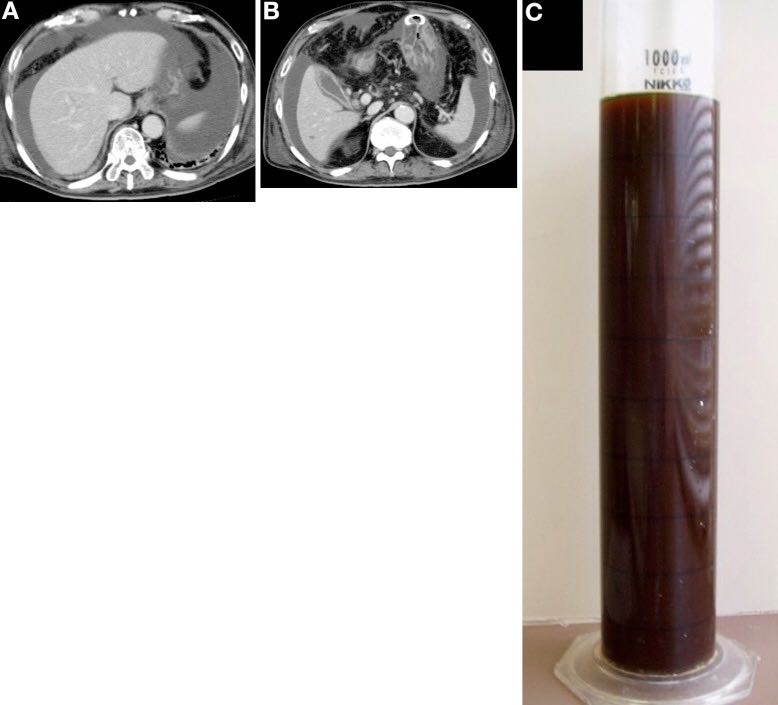

实验室检查结果显示:白细胞计数,44300/μL;血清白蛋白,2.6g;天冬氨酸转氨酶,1880U/L;丙氨酸转氨酶,1096U/L;胆红素,1.21mg/dL;C-反应蛋白,13.5mg/dL。 患者被诊断为感染性休克和急性肾功能衰竭并开始持续血液透析和机械通气。 腹部计算机断层扫描(CT)显示明显腹水(图A,B),诊断性穿刺显示为深棕绿色液体(图C),胆红素水平14.8mg/dL。